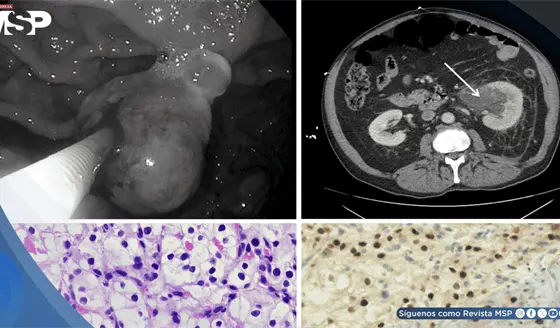

Metástasis gástrica permitió detectar cáncer en el riñón en paciente de 65 años con fibrilación auricular